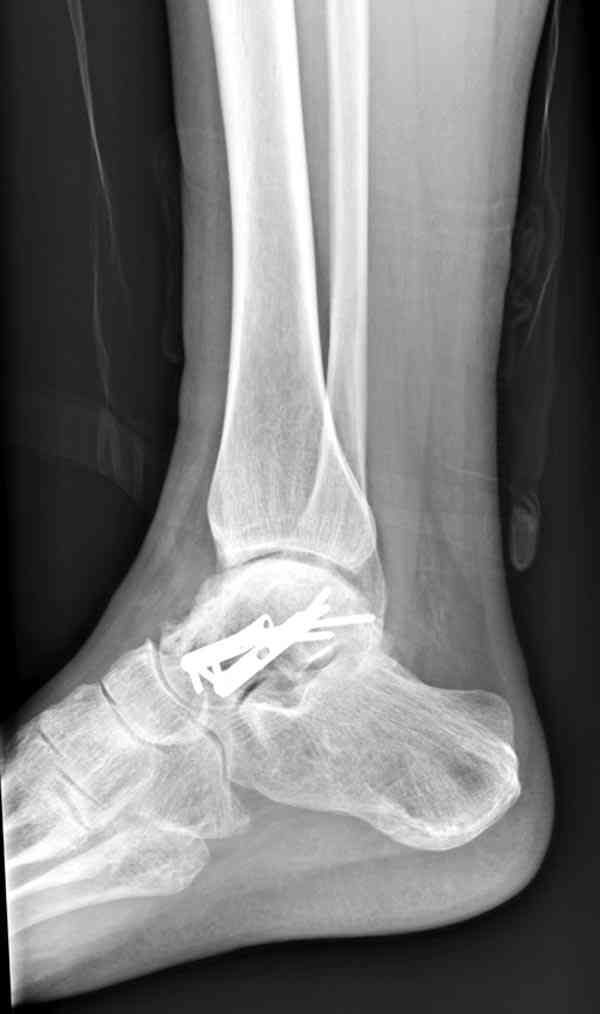

И второй случай из недавней ташкентской практики, (извините за качество ренгенограммы и только в одной проекции) случай падения с высоты (кстати моего друга - известного киноактера) - открытый

смещенный перелом тарана, с переломом переднего края дистального эпиметафиза большеберцовой кости.

При поступлении в приемной сделана первичная обработка с ушиванием открытой латеральной раны и вытяжением за пятку.

Из-за отсутствия времени пришлось оперировать на второе утро, из материала, что имеем на месте, фиксирован двумя шурупами, а третий-это контур сломанного жойстика в 4 мм. На дистальный медиальный конец тибиа antiglide 3.5 мм пластина. Через пару дней выписан и несмотря на предупреждение, самостоятельно начал нагрузку в 4 недели, время не ждет, снимается в боевике в Росийской Федерации.